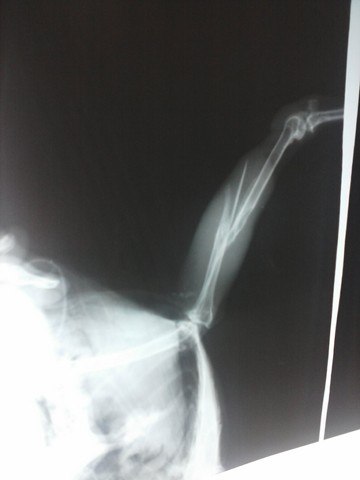

• У вороши перелом берцовой кости со смещением.

Сделан рентген в ЦВК, показана операция остеосинтеза.

26.06.12г. проведена операция, прогноз осторожный.

• Птишк уже после операции - на снимке видно внешнюю